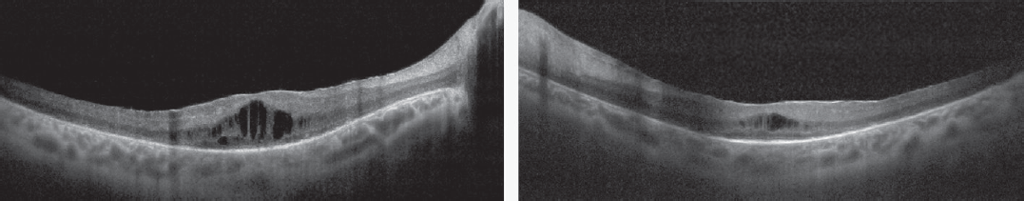

Пациент в возрасте 35 лет обратился на консультацию в Центр диагностики и хирургии заднего отдела глаза для получения «второго мнения» и определения тактики ведения. За два года до обращения в Центр диагностики и хирургии заднего отдела глаза на основании данных флюоресцентной ангиографии пациенту был поставлен диагноз идиопатического ретинального васкулита. В течение 1,5 года пациент получал циклоспорин А в дозе 350 мг и преднизолон (последний год в дозе 20 мг). На осмотре пациент предъявлял жалобы на низкую остроту зрения обоих глаз. Известно, что в возрасте 7 лет у пациента диагностирован миопический астигматизм средней степени обоих глаз. Дату снижения зрения пациент указать не может, считает своё зрение «плохим с детства». Максимально корригированная острота зрения (МКОЗ) правого глаза — 0,2, МКОЗ левого глаза — 0,2. Передний отрезок спокойный, клеток и флёра в передней камере нет. Визуа лизируется заднекапсулярная катаракта (больше на левом глазу), клетки в стекловидном теле (0,5+ для правого глаза, 1+ для левого глаза). На глазном дне на момент осмотра — диск зрительного нерва несколько гиперемирован, границы чёткие, артерии нормального калибра, вены не расширены, макулярный отёк, геморрагий нет; на средней периферии (больше в нижнем квадранте) зоны не ярко выраженных изменений по типу гипопигментации (рис. 1). При помощи оптической когерентной томографии (ОКТ) обнаружены макулярный отёк, разрушение наружных слоёв сетчатки (слой фоторецепторов практически полностью отсутствует), мелкие гиперрефлективные включения на уровне наружных слоёв сетчатки, гиперрефлективная структура на поверхности сетчатки (эпиретинальная мембрана) (рис. 2). Компьютерная периметрия выявила концентрическое сужение поля зрения до 10 градусов от точки фиксации (рис. 3). На серии флюоресцентных ангиограмм обоих глаз (рис. 4, 5) визуализировались ранние гиперфлюоресцентные дефекты (window-defect), гиперфлюоресценция макулярной зоны (макулярный отёк), выраженная гиперфлюоресценция перипапиллярно. Также был отмечен ликедж красителя из ретинального сосудистого русла на периферии.

Рис. 2. Оптическая когерентная томография (слева — правый глаз; справа — левый глаз)

Fig. 2. Optical coherence tomography (left — right eye; right — left eye)